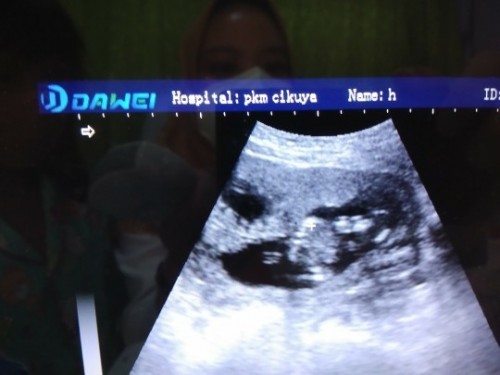

USG ada 2 kantong, tp yg terisi janin cuma 1. Yg 1 lg kosong

Moms, ada yg prnh ngalamin spt sy ga? Atau mngkn ada yg tau dan bisa menjelaskan. Uk sy saat ini 13w1d. Baru bngt kmrn USG dan trnyta terlihat 2 kantong, tp cuma 1 saja yg ada janinnya dan 1 nya lg kosong. Ini adalah kehamilan ke 2 sy. Kehamilan pertama sy melahirkan kembar non identik yg skrg sudah besar, 7 tahun. Sy di saranin cek lg ke SpOg tp bisanya selasa depan. Mhon sharingnya moms yg prnh ngalamin atau tau. Bahayakah kantong yg kosong itu? Mengapa bisa terjadi? Apakah ada efek nantinya? Selama TM1 ini sy baik2 saja, tidak ada flek atau keluhan lain. Hnya bawaan mulmun spt bumil biasa yg masi wajar. Jika ada yg prnh alami mhon sharingnya moms. Terimakasih #seriusnanya #bantusharing #ingintahu #pleasehelp #Usg